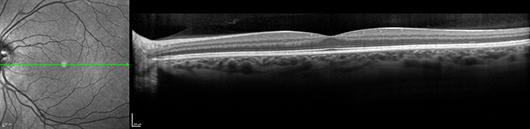

Optical Coherence Tomography (OCT) is an instrument that can be used for diagnoses and follow up of retinal and glaucoma problems. In glaucoma it is important that follow up scans are carried out to enable early detection of progression of the disease allowing early intervention and treatment.This instrument is also very sensitive in diagnosing and managing all retinal problems, such as Age Related Macular Degeneration (ARMD), pre-retinal membranes, macular holes, retinal swelling and other rarer retinal disorders.

The OCT is a non-contact medical imaging technology similar to ultrasound and MRI. With OCT, reflected light is used to produce detailed cross-sectional and 3D images of the eye.(1) These measurements are used to generate very precise cross-sectional images of the eye's anterior and posterior segment.

The OCT scan measures multiple wavelengths of reflected light across a spectrum. It acquires 40,000 A-scans per second. The increased speed and number of scans translates into higher resolution and a better chance of observing disease.

High speed image acquisition is combined with custom eye tracking technology to actively track the eye during imaging. Tracking eye movement with simultaneous dual-beam imaging minimizes motion artifact, enables noise reduction and allows the instrument to precisely track change over time. The result is point-to-point correlation between fundus and OCT scans, greater image detail and clarity, and is able assess small changes.